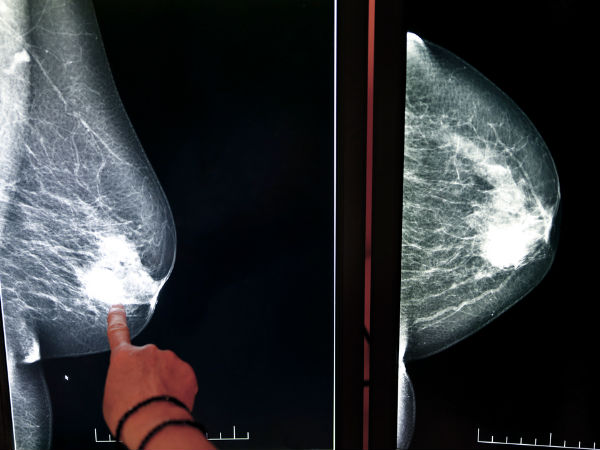

மமோகிராம்

சிலர் தவறான புரிதல் கொண்டுள்ளனர். மார்பக புற்றுநோயை கண்டுபிடிக்கும் மமோகிராம் என்கிற கருவியின் மூலம் x-ray எடுத்தால் புற்றுநோய் மேலும் பரவும் என நினைத்துள்ளனர்.

ஆனால், இந்த கருவி புற்றுநோயை கண்டறியவே, தவிர நோயை பரப்புவதற்கு இல்லை. இதன் x-ray தாக்கம் மிக குறைந்த அளவு என்பதை நினைவில் கொள்ளுங்கள்.